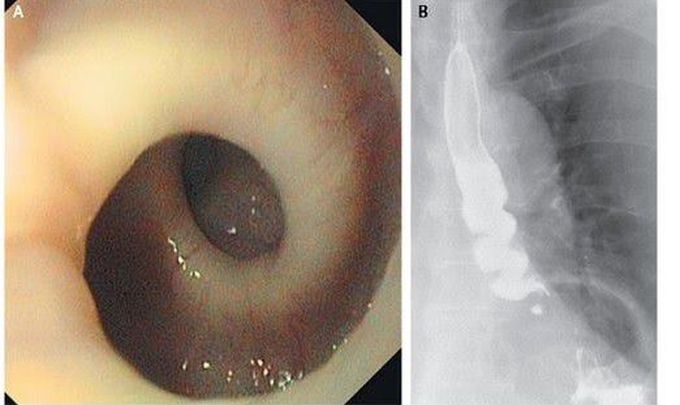

"Twisted Esophagus"

An 87 year old woman in Switzerland went to a doctor complaining that she painfully spasms everytime she swallowed. The image above was the x-ray of her esophagus that is twisted in a corkscrew shape.

This is not a spasmodic condition.. congenitally having a spiral shaped oesophageal wall